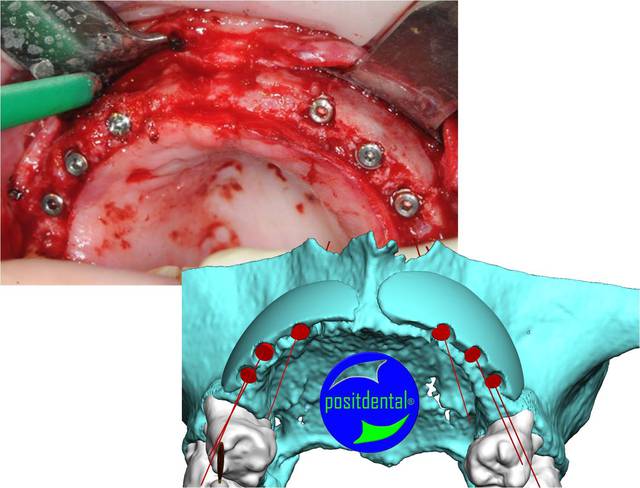

Nous ne sommes pas sur la même longueur d’onde. Lorsque tu m’as demandé de travailler sur le projet, Biobank n’était pas en mesure de répondre à ta demande. J’ai réalisé une procédure confidentielle pour usiner un greffon de façon manuelle dans des conditions de livraison respectant les données acquise de la science. Comme pour le développement du guide chirurgical j’ai pris le maximum d’information pour connaitre les critères à respecter, un des critères (et cela peut répondre à l’interrogation de pluton) la partie corticale semble être plus longue à se résorber et permettre une meilleure formation osseuse, ce que l’on voie souvent dans ce type de reconstruction ce sont plusieurs greffons en domino ostéosynthésés et souvent en spongieux plus facile à conformer après ouverture du lambeau. Ce que j’ai constaté dans ce genre de procédure se sont des manques de formation osseuse à la jonction des bouts de greffons comme sur l’extrémité des 2 greffons.

Faisons un peu de prospective, je joins la photo 3D réalisé y a plusieur mois montrant ce qui est espéré et la photo que tu à mis en ligne sur eugenol, chacun sera en mesure de jugé de la qualité du résultat obtenu.

> Faisons un peu de prospective, je joins la photo 3D réalisé y a plusieurs mois

> montrant ce qui est espéré et la photo que tu à mis en ligne sur eugénol, chacun

> sera en mesure de jugé de la qualité du résultat obtenu.